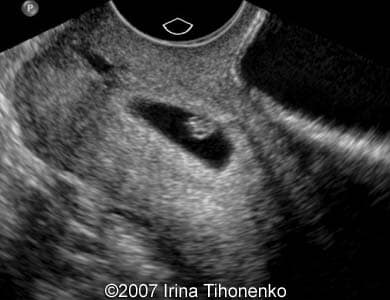

Following images show a case of the cervical gravidity.

Images 1, 2:Ā Image 1 represents a sagittal transabdominal view showing the uterus with dilated cervical canal due to the cervical pregnancy. Image 2 shows detailed view at the cervix with the embryo inside.